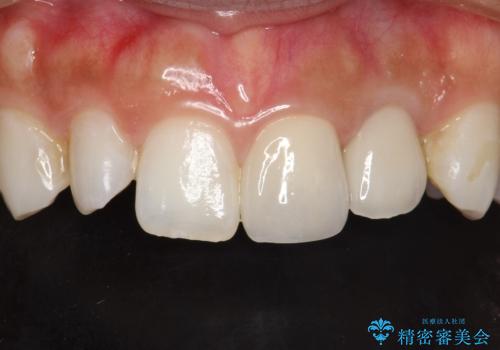

レントゲン上でも適合の良いかぶせ物が装着できています。